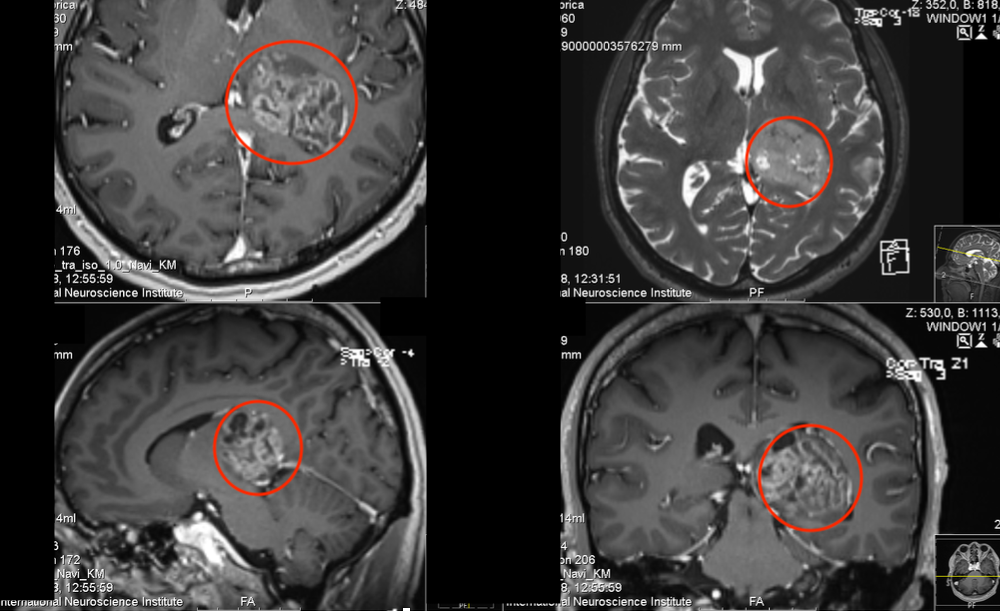

在5-ALA荧光、术中神经导航和术中MRI辅助手术,通过左侧顶枕枕骨开颅术和显微外科肿瘤全切手术,手术顺利,无手术并发症。

术中磁共振检查,显示肿瘤准确全切

(红色表示切除前,绿色表示切除后)